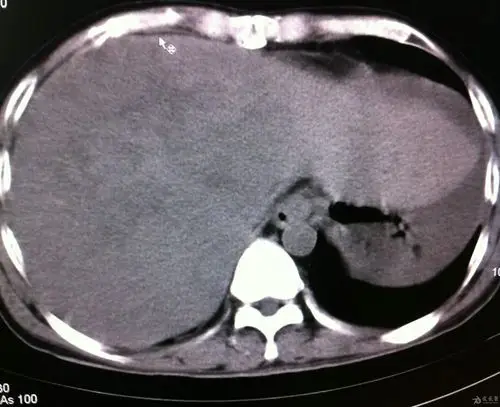

术中发现肝右前分支血管破裂,造影剂外溢!

肝破裂.jpg

ct在诊断肝损伤中的价值